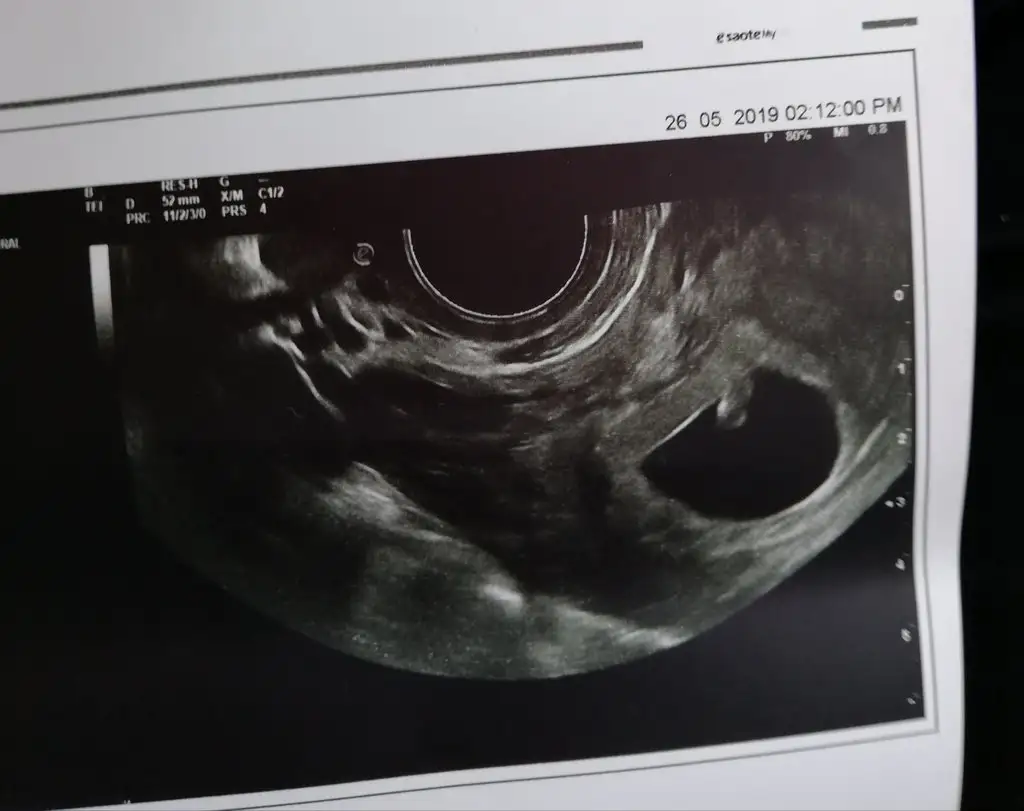

Kizlar banada yorum lutfen 1.resim 6 haftalik vajinal

2.resim 7 haftalik karindan usg